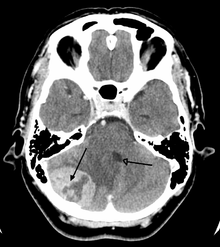

A posterior fossa tumor leading to mass effect and midline shift

Most of the brain is separated from the blood by the blood-brain barrier (BBB), which exerts a restrictive control as to which substances are allowed to pass. Therefore, many tracers that reach tumors in the body very easily would only reach brain tumors once there is a disruption of the BBB. Thus the disruption of the BBB, which can be detected by a MRI and CT, is regarded as the main diagnostic indicator for malignant gliomas, meningiomas, and brain metastases.[21]